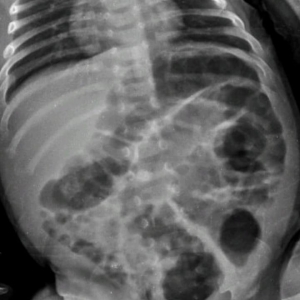

Na manhã desta segunda-feira (07) a 20ª Subdivisão Policial de Toledo divulgou o resultado das investigações acerca de uma tentativa de homicídio praticada contra um bebê, na época com aproximadamente 40 dias, onde os pais do infante eram os suspeitos.

O caso ocorreu no início do mês de julho, sendo os pais investigados inicialmente presos temporariamente por 30 dias.

Durante este período as investigações transcorreram e foi possível reunir ainda mais evidências do envolvimento dos pais da criança no caso, fato este que ensejou representação pela Prisão Preventiva, a qual foi determinada pelo Poder Judiciário, seguindo os pais da criança (21 e 22 anos de idade) agora presos por tempo indeterminado enquanto aguardam o andamento do Processo.

O Delegado Rodrigo Baptista Santos disse que "a postura dos investigados em sustentar uma versão absurda para os fatos constatados, dizendo que não tinham notado os hematomas, os quais surgiram repentinamente, acreditando serem reações alérgicas de uma picada de mosquito, caíram por terra com os Laudos e exames que atestam a gravidade das lesões e o risco a vida do qual o infante foi exposto".